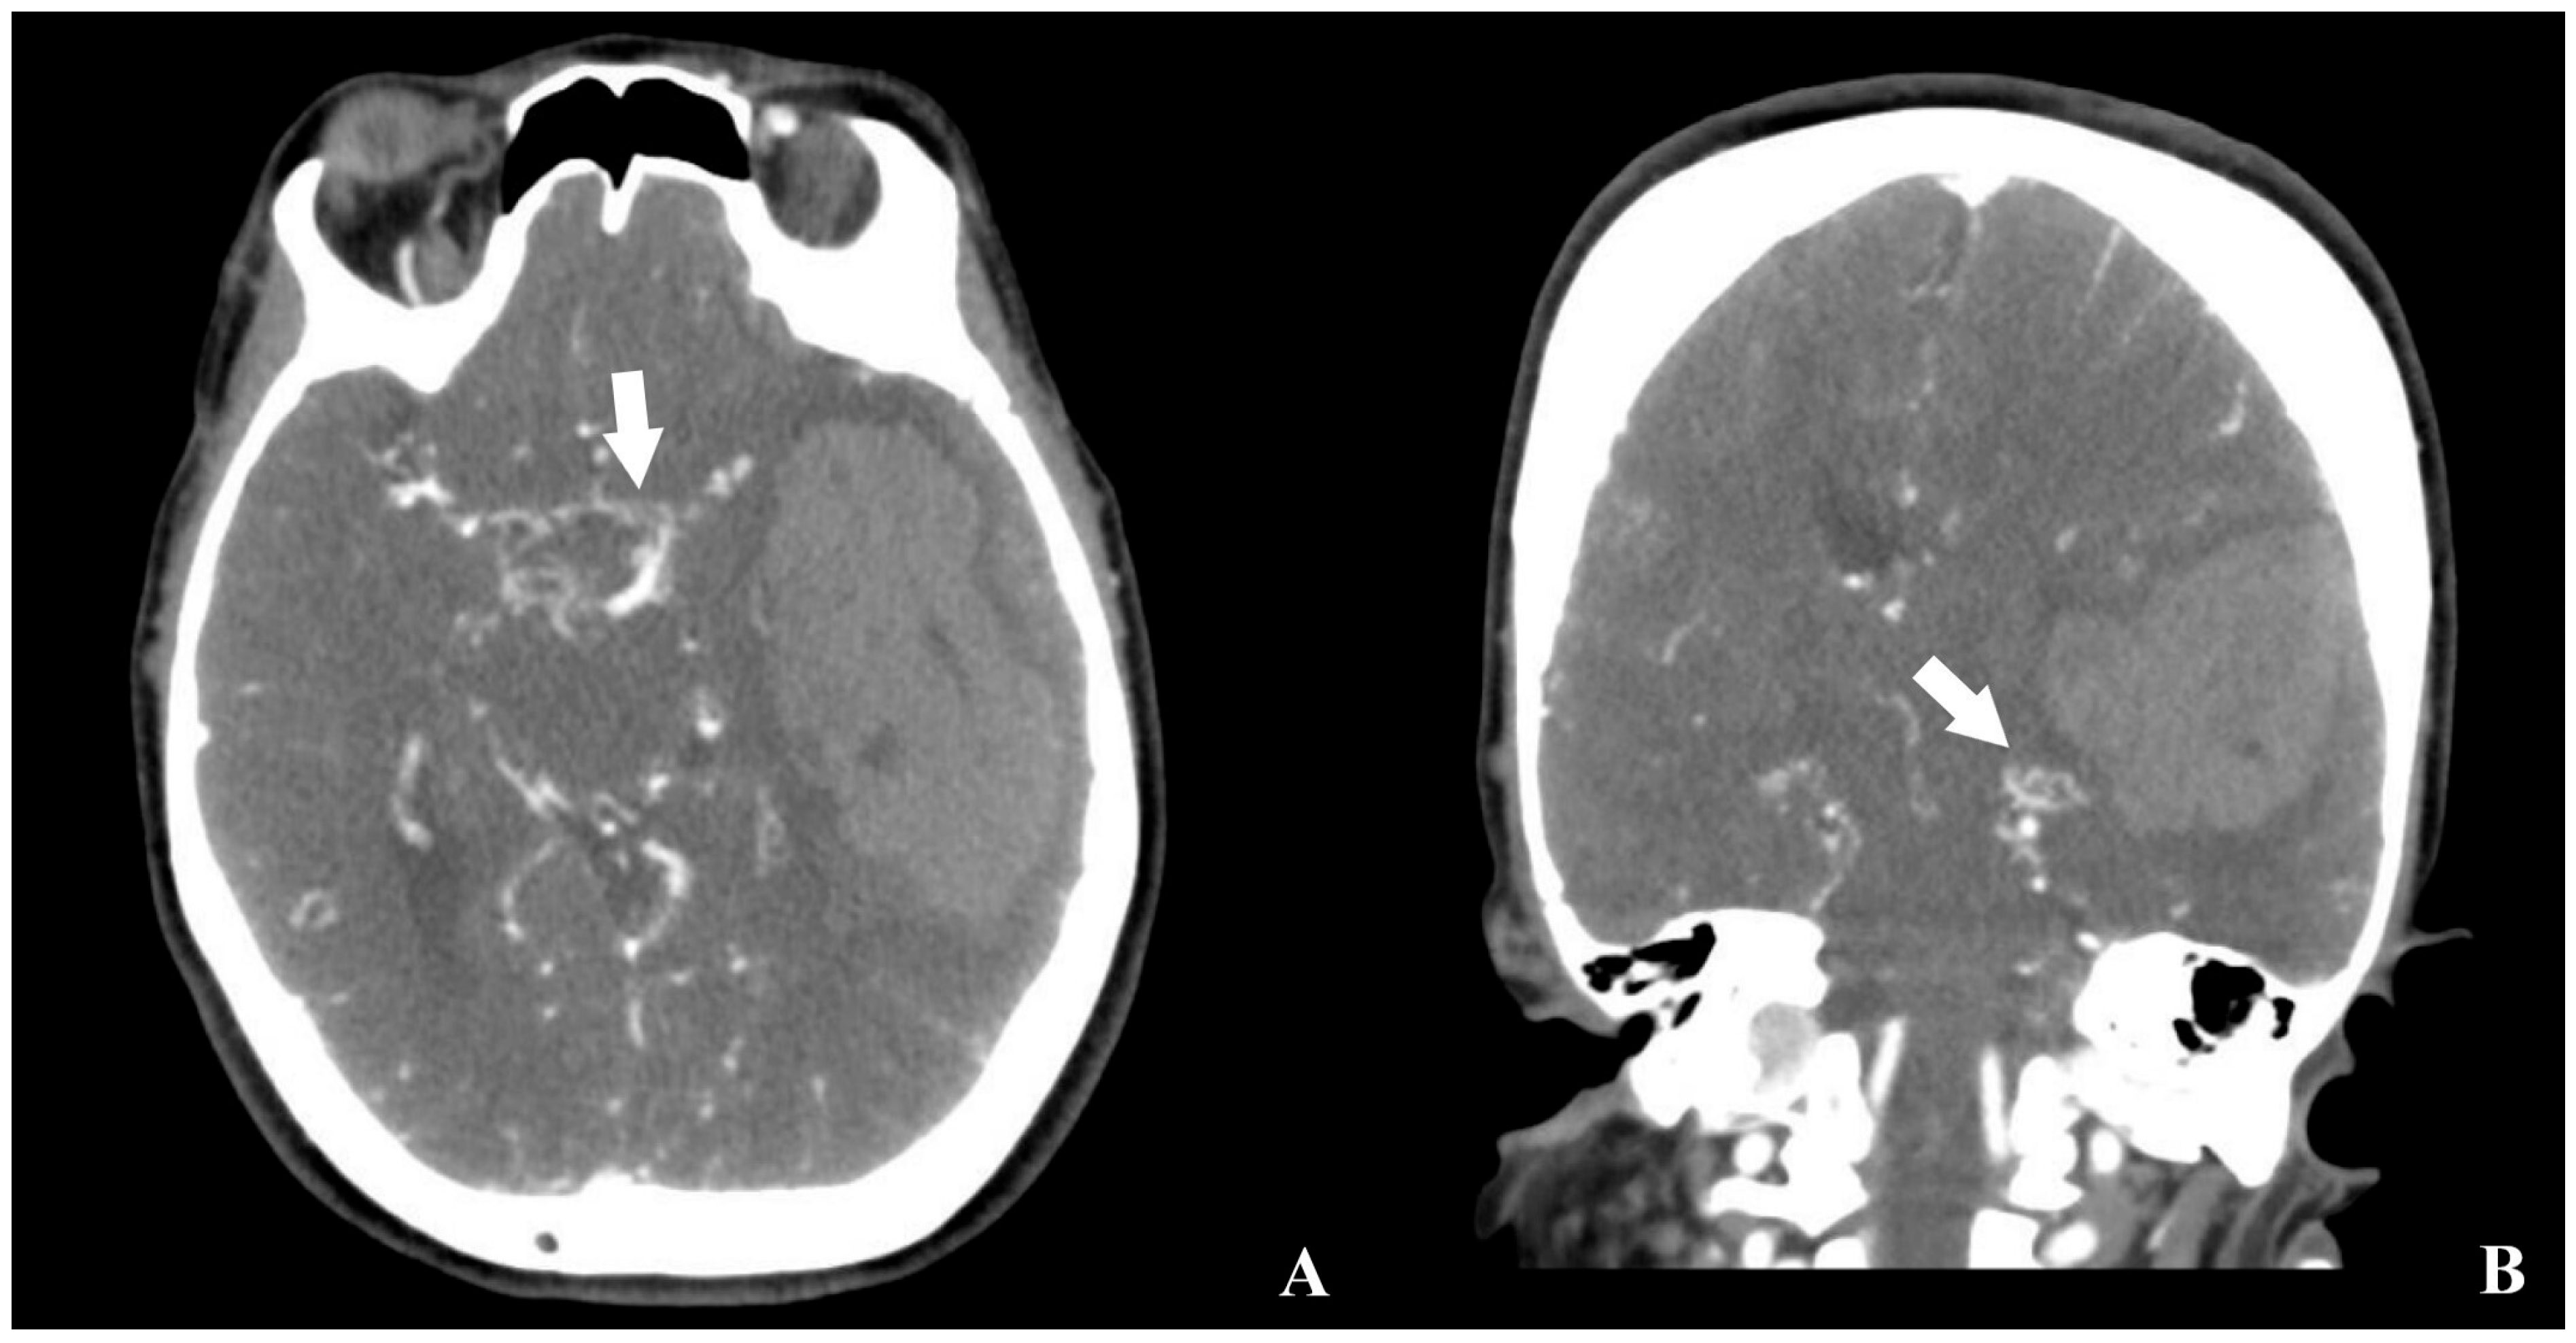

2. Case Description